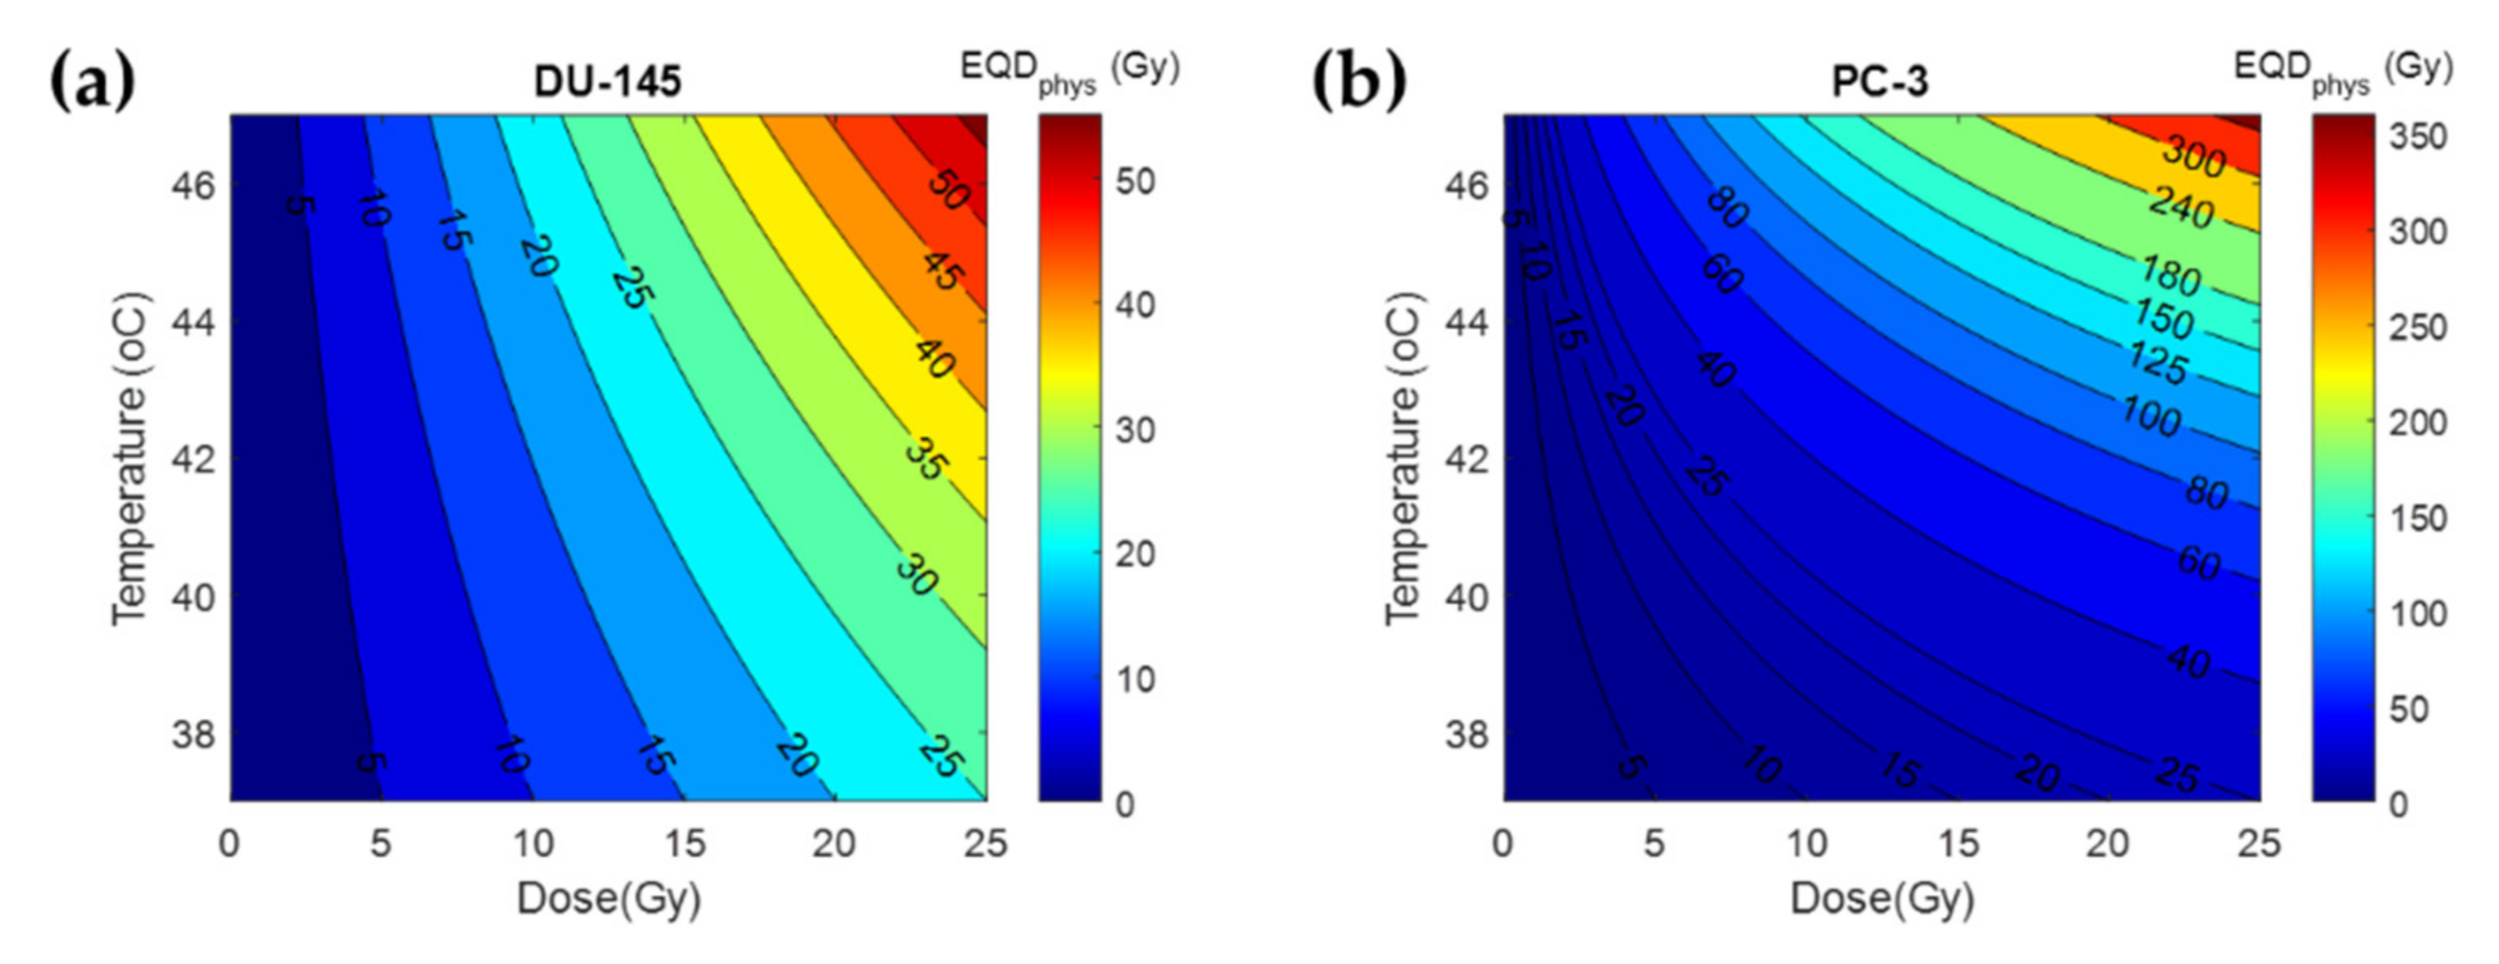

3.2. Thermal Radiosensitization

3.3. Treatment Planning Results